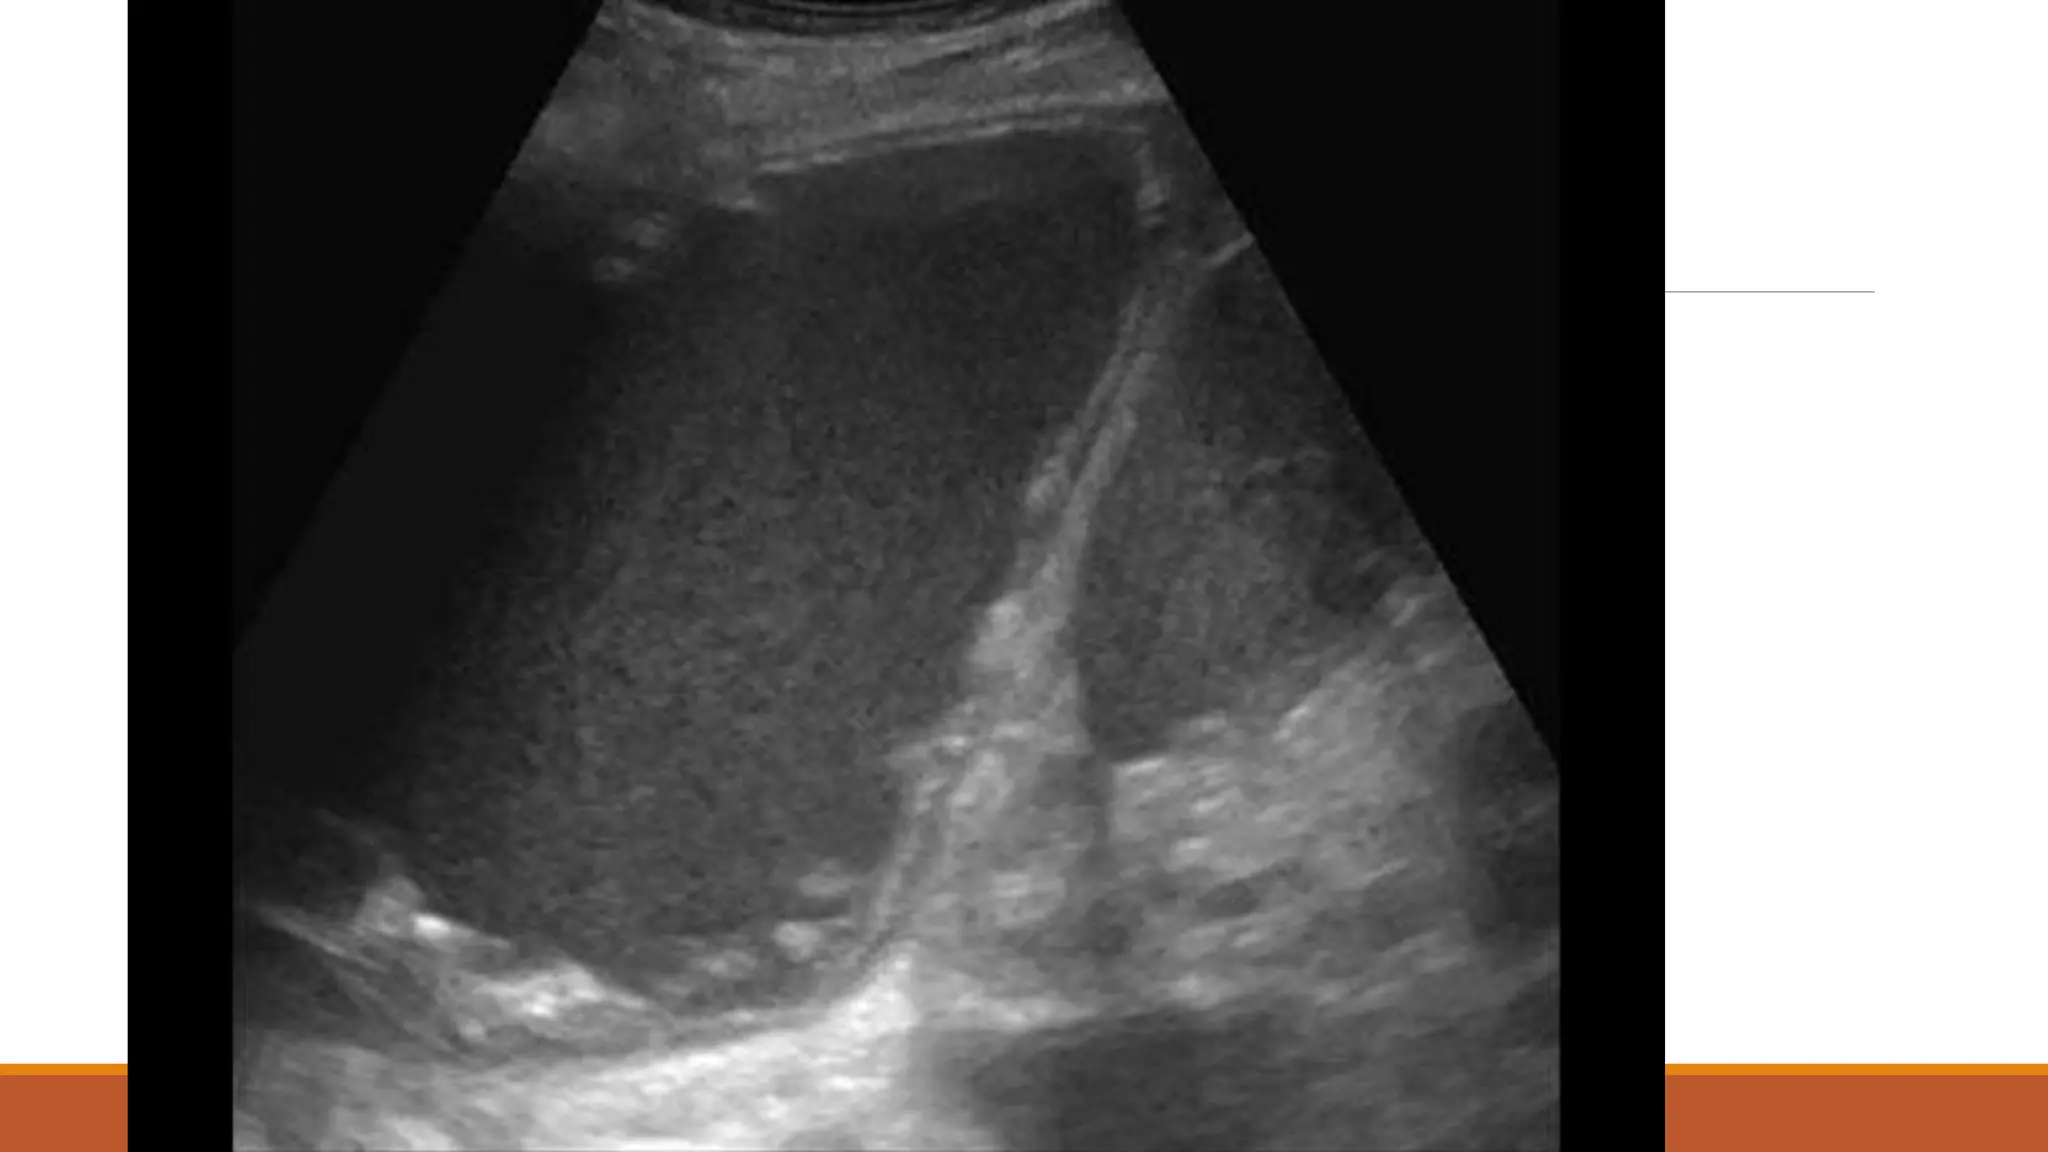

63 male

Normally F&W, no regular medications

Became unwell 7th Dec 2020 – cough, yellow sputum

Saw GP 23rd Dec – oral doxy

No real improvement – Clarithromycin 6/1/21

Again no improvement

Progressive loss of appetite and weight over a couple of months – given fortisip, which stopped

weight loss, but poor appetite continued

Progressive right shoulder pain and inability to lie on left side due to dyspnoea

On examination

OE: Acutely distressed, in significant pain and sats dropped to 80% when sat forwards, but 98%

when reclined at 60 degrees

Chest – no air entry right side

Results Fluid LDH >50000 pHunable due to viscosity Protein 63 Glucose <0.6 Fluid grew Streptococcus anginosus